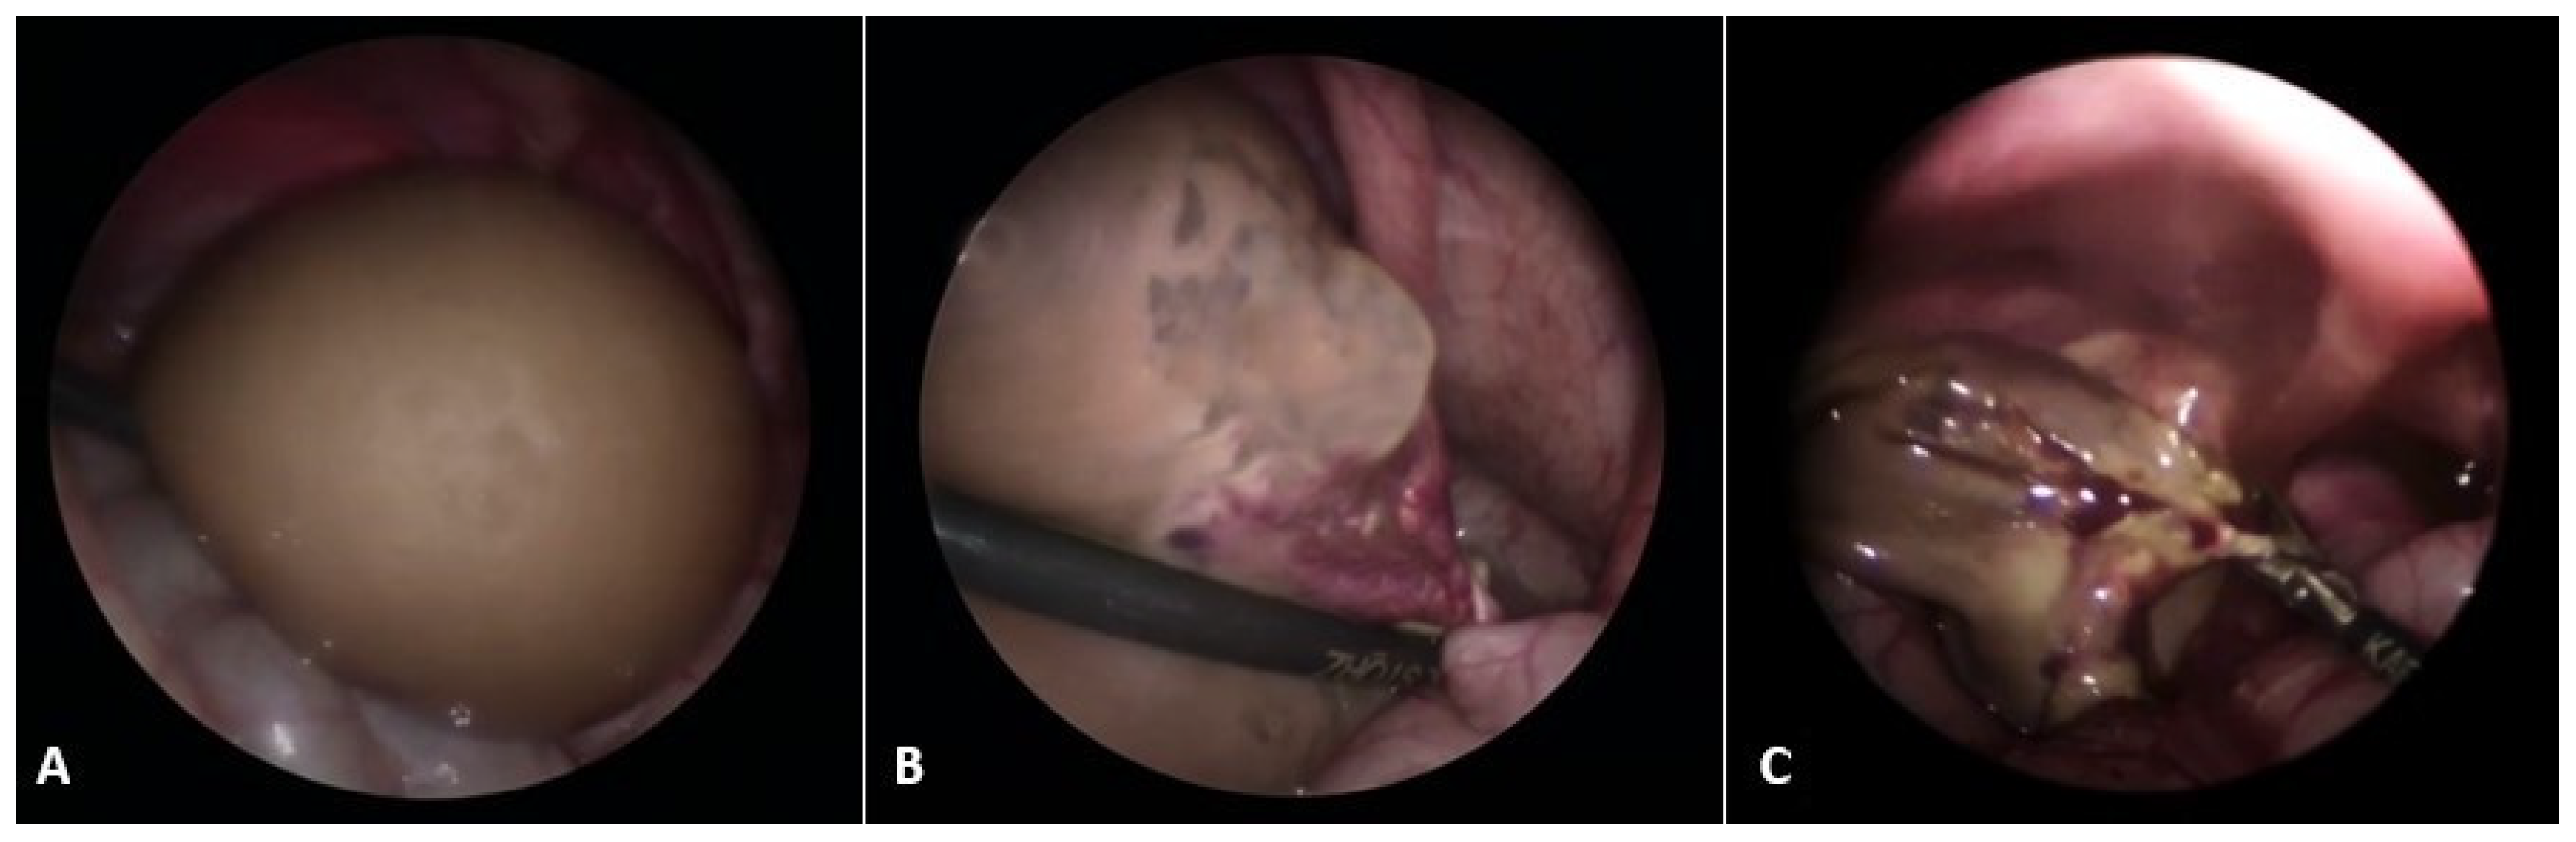

Figure 1.

A 7-day-old female neonate presented with a large abdominal mass. (A) Laparoscopic examination revealed a necrotic, twisted, huge neonatal ovarian cyst measuring 6 × 5 × 4 cm; (B) Twisting of the ovarian pedicle by 720 degrees; (C) After decompression of the cyst, a laparoscopic salpingo-oophorectomy was performed due to the obvious necrosis of the ovarian tissue. Source: Archive of the Department of Pediatric Surgery, University Hospital of Split.